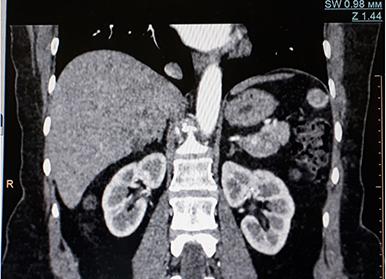

Компьютерная томография головы является одним из самых популярных способов диагностики, применяемых в современной медицине. С его помощью можно получить полное представление о состоянии здоровья головного мозга, а также прилегающих костных структур и мягких тканей. Как проходит такое сканирование, и что оно показывает, в каких ситуациях назначается врачом, а каким пациентам противопоказано – ответы на эти вопросы вы найдёте в представленной ниже статье. Также мы сообщим о мерах предварительной подготовки и о болезнях, которые может обнаружить этот метод. Также предоставим вам информацию об альтернативных методах диагностики, о преимуществах КТ и томографии с контрастом.